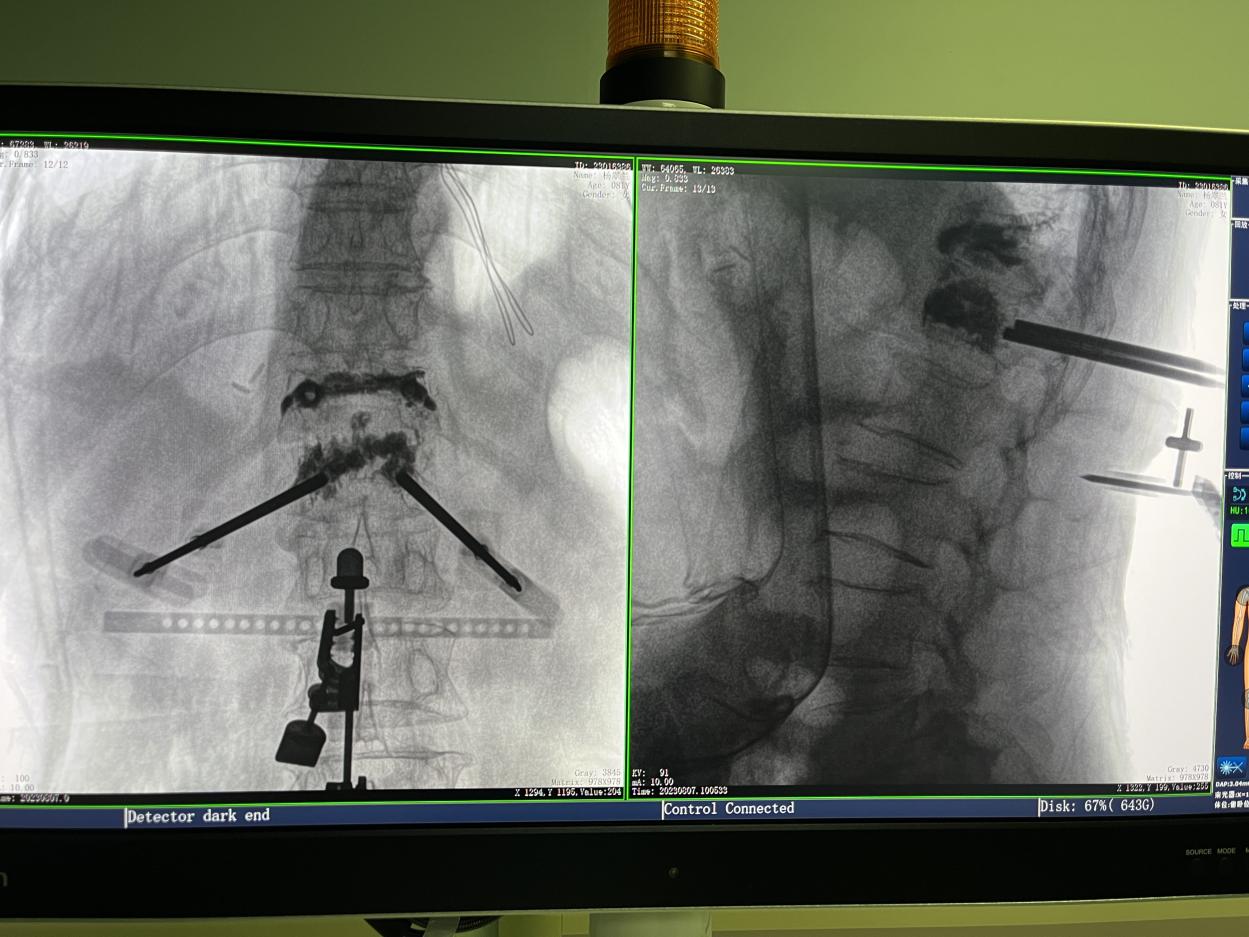

1.三維術中圖像

PL300B搭配普愛醫療自主研發生產的平板三維C形臂使用,通過三維立體術中圖像,手術醫生可從各個方位觀察合適的手術入路,并進行關鍵數據測量,從而最大限度地避開危險區。

骨科機器人手術-術中影像